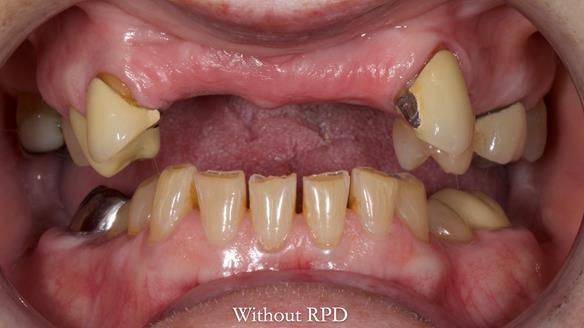

This is one of those cases that reminds me why I love removable prosthodontics. Pam was an absolute joy to treat — we were on the same page throughout. Her old upper flexible denture was loose, uncomfortable, and unaesthetic. We replaced it with a carefully designed metal-based upper partial denture/splint and new porcelain-bonded-to-zirconia (PBZ) crowns for the canines. The result is stable, comfortable, and natural-looking.

- Diagnosis and plan – Flexible upper denture ill-fitting with poor stability, retention, and appearance. Plan: metal-based upper partial denture/splint with lighter porcelain-bonded-to-zirconia crowns on UR3 and UL3.